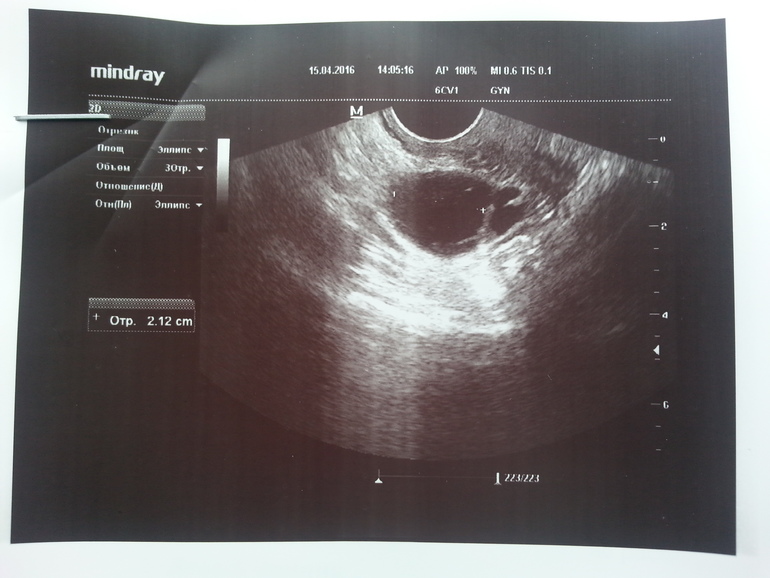

Добрый день девочки)очень нужно ваше мнение по поводу фолликулометрии, сегодня 15дц узистка написала в заключение в пя фолликулярная киста 21.2мм, но разве это не норм размер фоллика который должен лопнуть? Или я ошибаюсь.

Вот и я удивилась про кисту, еще ее переспросила она мне в ответ что фоллик должен был лопнуть.